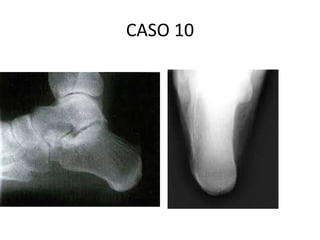

CASO 10

• SRM, 42ª, corredor de fds, sofre uma dor em

paturrilha q kimita de correr ha 2 semanas.

“doutor, parece q levei uma pedrada no

cibit”(sic).

• Comente imagem

• Exame fisico

• HD

• ex.complentares